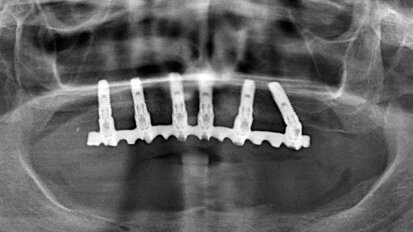

Alla ricerca della combinazione ideale tra capacità di creare spazio e ridotta invasività

Il dr. Mauro Merli ha sviluppato la cosiddetta “Fence Technique”. Con questo approccio è possibile favorire la rigenerazione di ampi ...